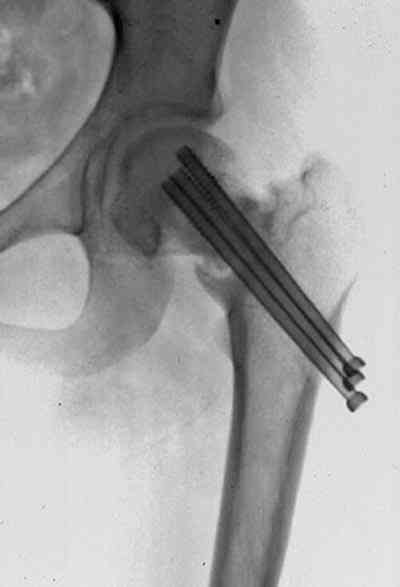

На снимках ложный сустав шейки бедра, несостоятельность фиксации. По положению шурупа можно предсказать ложный сустав, например, если screw backup за кортикальный слой около 15-20 мм, и также изменение угла от первоначального.

№2-3 типичная ошибка несоблюдения концепции параллельности шурупов, нарушение-фиксация поперечным допольнительным шурупом для приближения отломка в результате не сработало метод параллельных шурупов